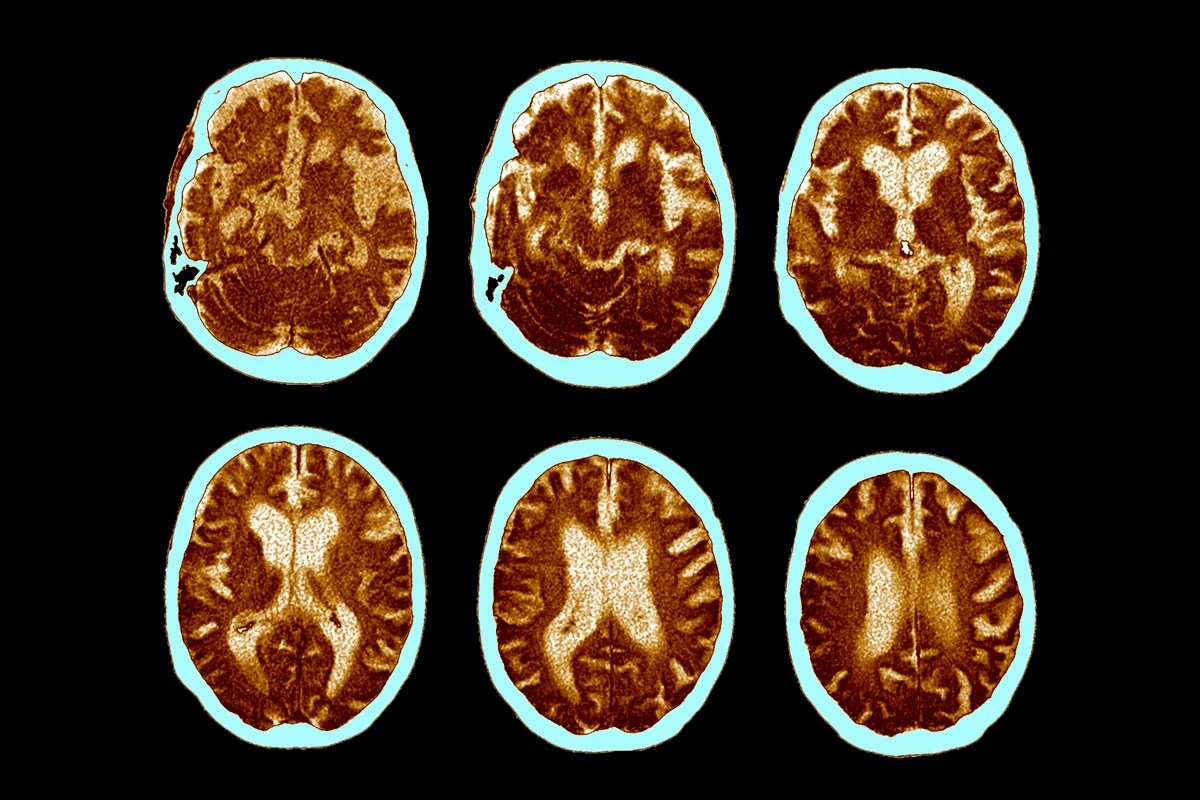

Structural MRI Findings

Structural MRI is a powerful tool for looking at neurodegeneration in Alzheimer’s. It shows changes in the brain, like in the hippocampus and entorhinal cortex. Atrophy in these areas is a big sign of neurodegeneration.

With MRI, we can measure brain region volumes and track changes over time. This is important for diagnosing Alzheimer’s and seeing how it progresses. For example, studies show that hippocampal atrophy is a good marker for Alzheimer’s disease.